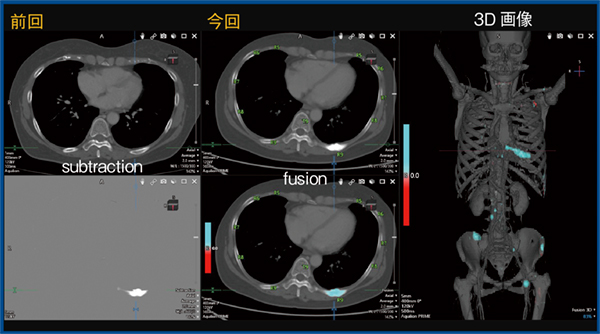

4.乳がん,多発溶骨性骨転移,化学療法中

TSBは,新たな転移病変の検出だけでなく,既存の骨転移の経時的変化の評価にも有用であり,骨転移の病勢の把握や,化学療法やホルモン療法の治療効果の評価も可能である。図4は,乳がんのリンパ節転移,肝転移,多発骨転移に対する化学療法中の症例である。前回のCTでは溶骨性変化が散見されるが,治療により硬化した病変が青く表示され,治療効果が一目で把握できる(図4 →)。

図4 乳がん,多発溶骨性骨転移,化学療法中